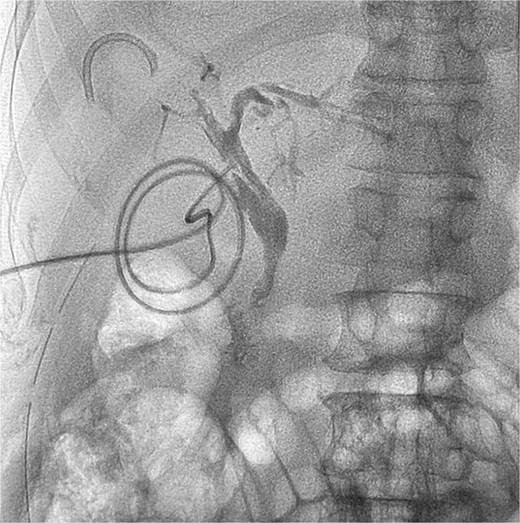

Two patients (33.3%) underwent percutaneous transhepatic biliary drainage (PTBD) to relieve biliary obstruction and control cholangitis. They presented with severe sepsis and were considered unfit for immediate endoscopic or surgical intervention. Endoscopic stent and stone removal via ERCP were successful in two patients (33.3%). In the remaining patients, endoscopic interventions were unsuccessful, necessitating surgical exploration of the CBD.

During surgery, the stents were removed along with stent-associated stones (“stentoliths”) and other calculi from the bile ducts (Fig. 2). Intraoperative choledochoscopy was used to confirm complete clearance of the bile ducts. Stone clearance was achieved in all patients except one, where small stone fragments in the intrahepatic ducts could not be fully removed.

Isolated specimen of intraluminal stent and associated stentoliths.